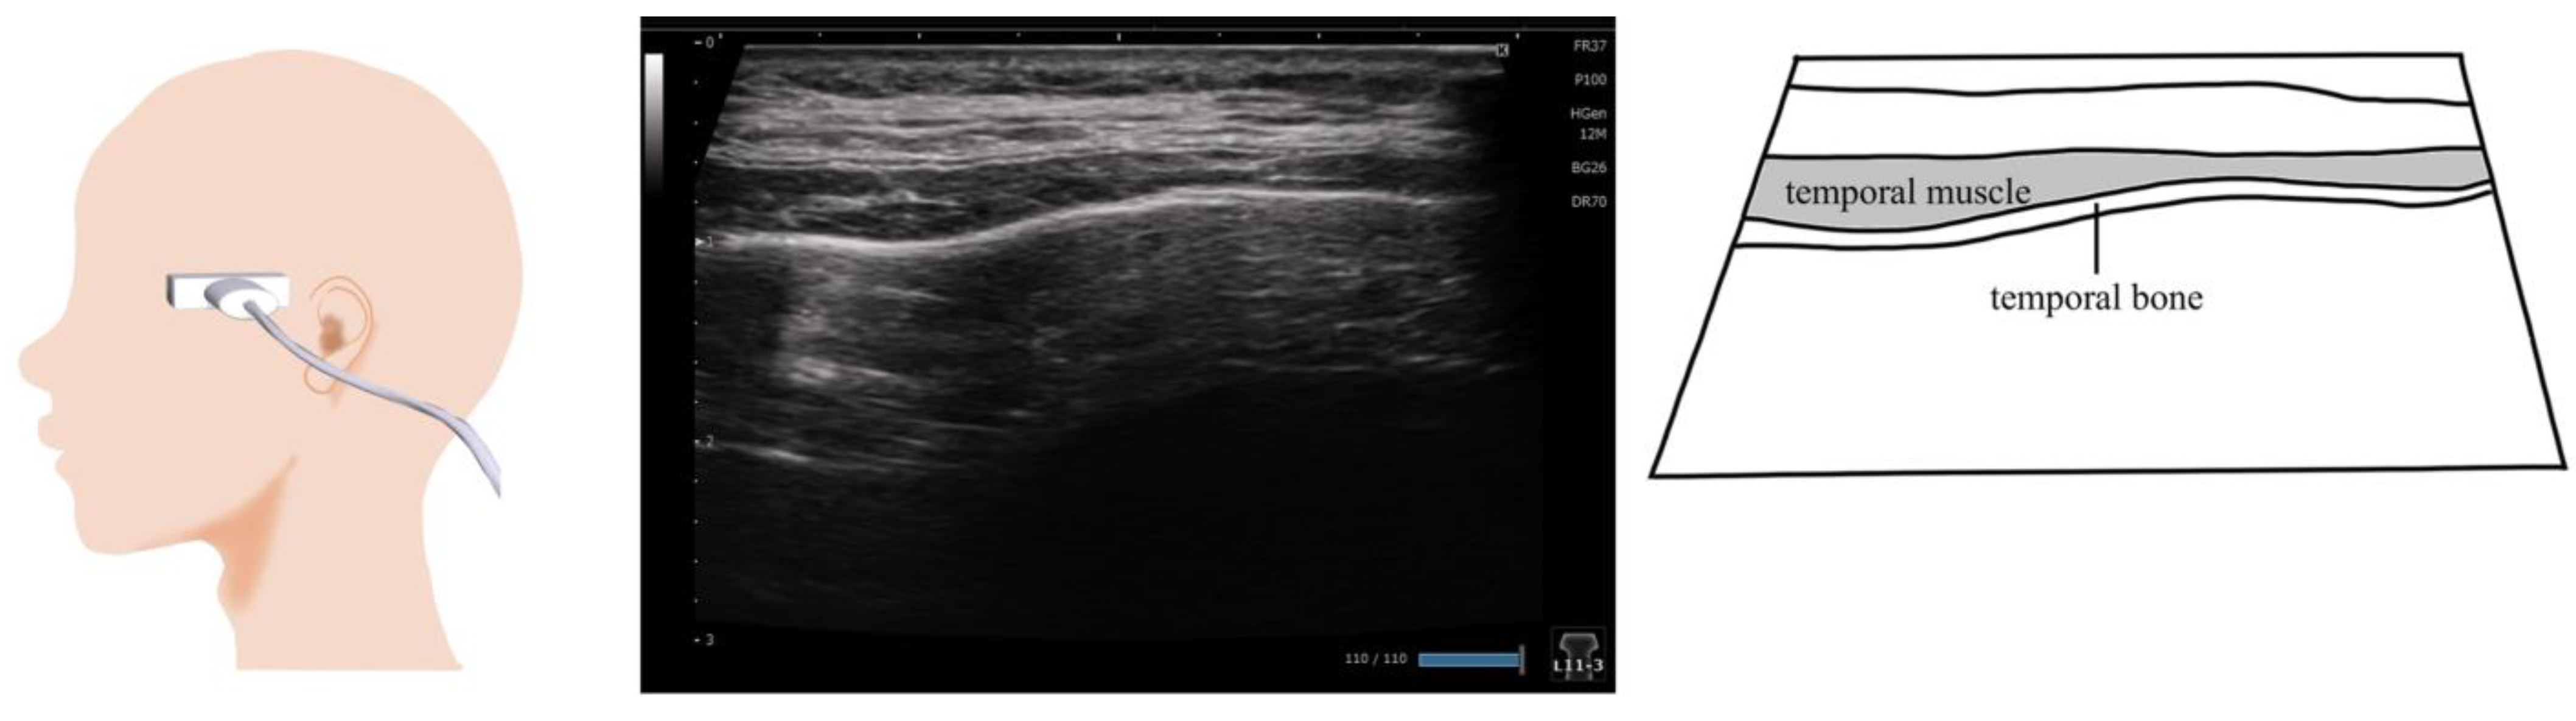

10. Temporalis Muscle (Figure 9)